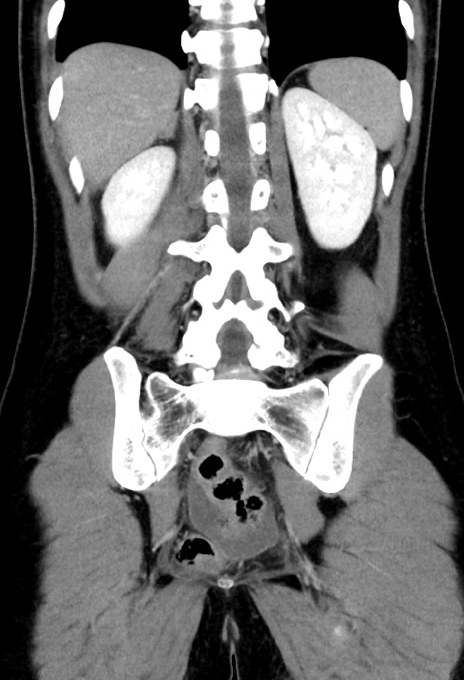

症例17(冠状断像)

【症例】20歳代女性

【主訴】嘔吐、下腹部痛

【現病歴】昨日夕食後に嘔吐し下腹部痛が出現。本日になっても嘔吐持続し改善しないため来院。

【身体所見】意識清明、BT 37.2℃、BP 108/67mmHg、腹部:平坦、やや硬、下腹部正中から右にかけて圧痛あり、反跳痛軽度あり、tapping pain(+)。

【データ】WBC 13600、CRP 14.94